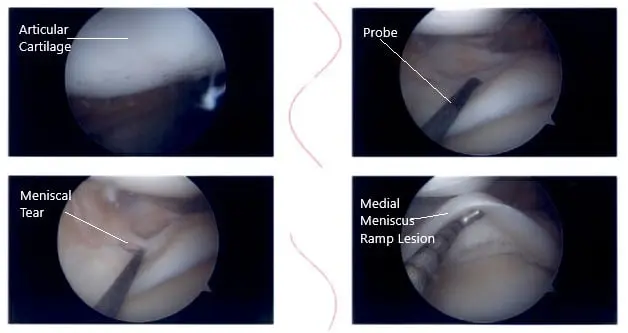

Now the scope was moved to the internal trochlear area where ACL was deficient.  Debridement was done. The scope was moved to the lateral compartment where we found medial edge fraying as well as a small bucket handle tear of the medial edge of the lateral meniscus. The medial edge was debrided.

Further examination showed a horizontal tear going up to the periphery of the lateral meniscus of the posterior body.  The decision was made to repair this tear.  Three FasT-Fixes were used for repair of the lateral meniscus, horizontal lesion.  Before that, a posterolateral incision was given anterior to the fibula.

Intraoperative knee arthroscopic images 3

Intraoperative knee arthroscopic images.

With sharp and blunt dissection making a plane behind the LCL and between the knee capsule in the lateral head of gastrocnemius, a plane was made.  Sims speculum was inserted to protect the posterior neurovascular bundles.  After it was done, the scope was reentered and the repair of the left meniscus using FasT-Fixes was done in a satisfactory fashion.  All the arthroscopic pictures were saved.  Microfracture of the trochlear notch was performed using bundle fix.